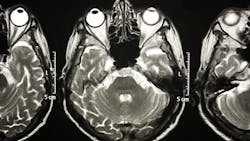

Royal Philips has announced two new advances in MR-only workflows to advance head and neck cancer radiotherapy imaging and simulation. The company’s artificial intelligence (AI) enabled MRCAT Head and Neck radiotherapy application, which allows the use of MR as the sole or primary imaging modality for radiotherapy planning in the treatment of soft tissue tumors in the head and neck, along with the brain, pelvis and prostate, has received FDA 510(k) clearance and is commercially available in the U.S.

As a result of a recent development partnership with patient-positioning company MacroMedics, Philips has also announced compatibility of MacroMedics’ latest DSPS (Double Shell Positioning System) ProminentTM positioning system [1] with Philips MR Head Neck Coil. This unique solution combines the superior soft tissue imaging capabilities and the high-resolution image quality of Philips’ head and neck coil with the comfort-enhancing and positional accuracy and stability features of MacroMedics’ mask. These developments aim to improve the accuracy of radiotherapy planning and simulation to help achieve better patient outcomes, enhance patient comfort, and offer the efficiency benefits of an MR-only workflow.